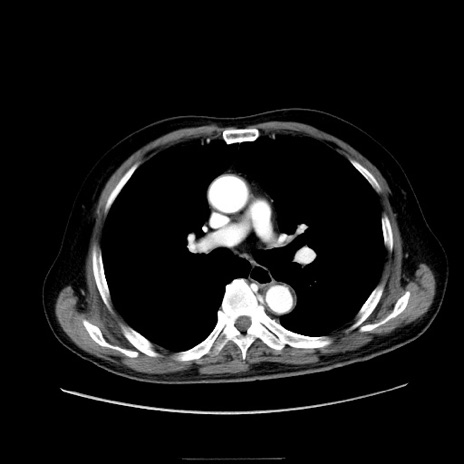

冠状断像

【症例】80歳代男性

【現病歴】約6時間前から臍下部痛が出現。次第に腹部膨隆・背部痛も生じてきたため来院。背部痛の場所は変化しない。

【身体所見】意識清明、BT 36.3℃、BP  131/87mmHg、P 87bpm、SpO2 100%(RA)、臍周囲自発痛・圧痛あり、反跳痛なし、自発痛部位に一致して板状硬あり、腹部膨隆、腸雑音減弱、CVA tenderness両側陰性。